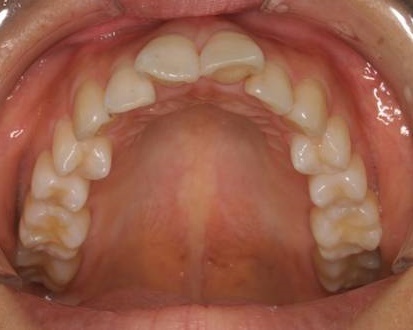

Case 2

主訴:  噛みにくい

診断:  アングルⅠ級 叢生

治療方針:

患者さんは26歳の女性で、上下顎の叢生による審美障害と咬合異常を訴えた。セファロ分析の結果、U-1 to FHおよびL-1 to Mandibularは1S.D.を超えて小さい値であった。その為、上下顎の叢生量は大きいが、上下前歯部の舌側傾斜による口元の落ち込みを防止する目的で、非抜歯で治療を行うことにした。

治療期間: 1年4カ月

費用:

診断費30000円、装置費用600000円、保定装置費用50000円、月1回の調整費4000円  (全て税別)

【 治療前 】

【 治療後 】